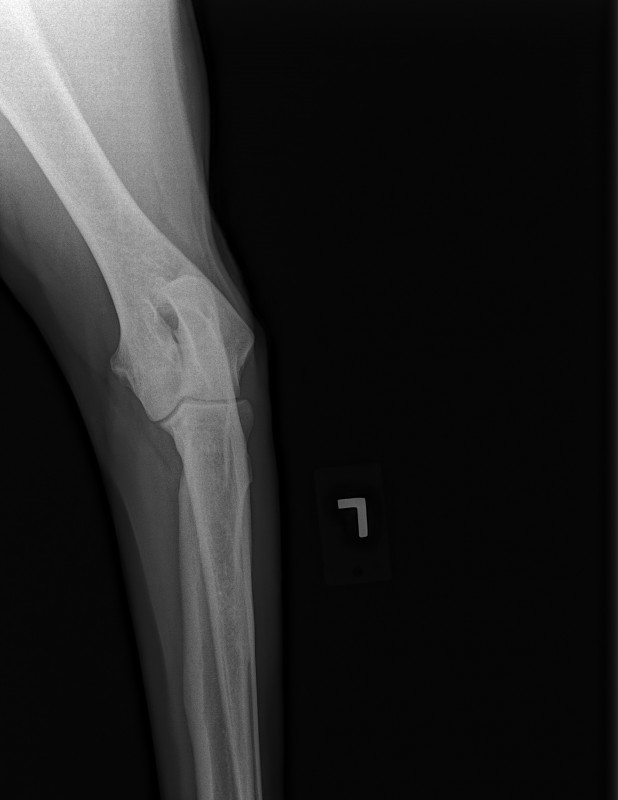

The current size of his mass is 8.2 cm x 10 cm x 21 cm. This is an extremely RARE cancer – less than 1%.

To further complicate matters, this mass has herniated down into his thigh and groin severely compromising his ureter and femoral nerve. He has had three CT scans of which his latest has shown that to date his chest remains clear of metastasis and his lymph nodes are not enlarged. His MRI has shown that his case is extremely complicated and the surgery he shall specifically require, scheduled for March 23rd has ONLY ever been done twice before by the two expert surgical oncologists assigned to him.